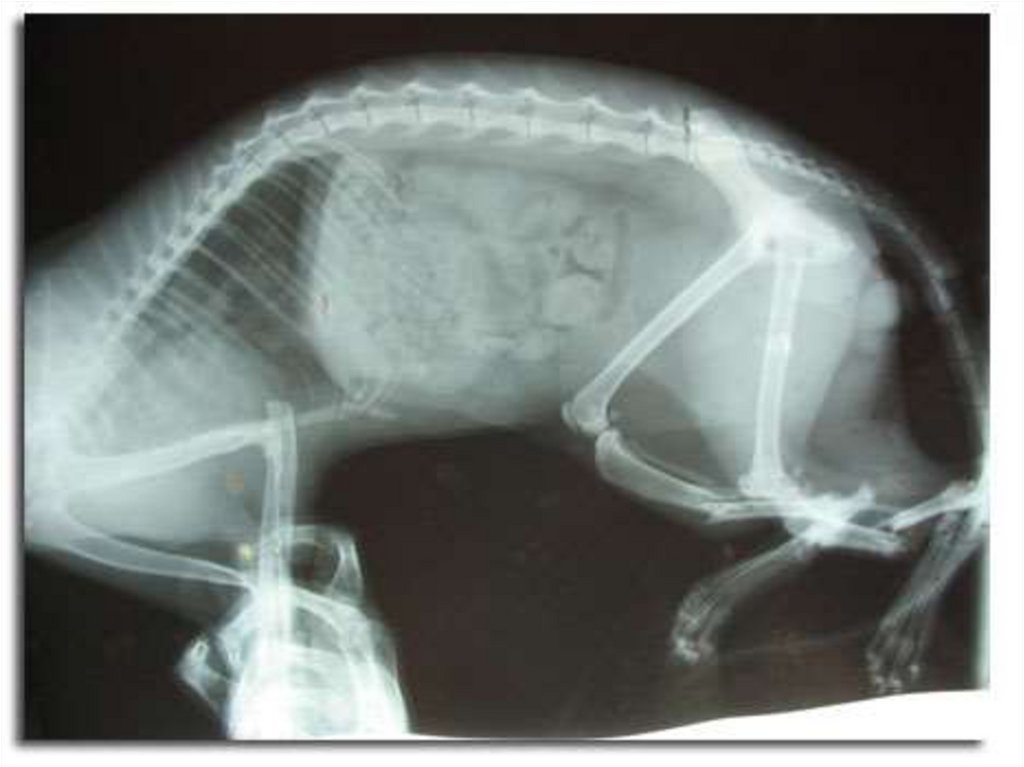

рентгенологический и его модификации (рентгеноскопия,

рентгенография, рентгенокимография);